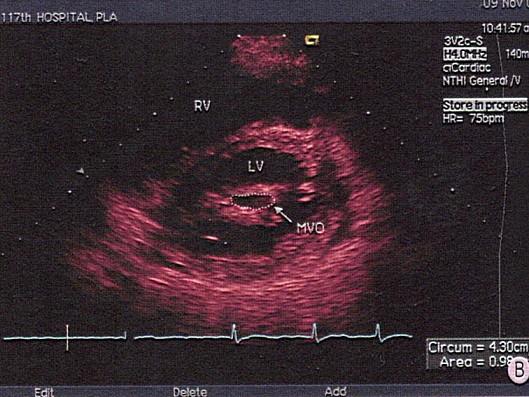

问题 该图所显示的病例为?(?)

选项 A.二尖瓣腱索断裂 B.二尖瓣脱垂 C.二尖瓣赘生物 D.风心二尖瓣狭窄 E.黏液瘤

答案 D